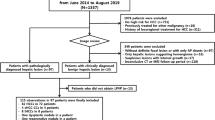

Study population

We enrolled consecutive patients diagnosed with HCC by routine imaging who underwent DCE-MRI with Gd-BOPTA from June 2013 to August 2016 and patients who underwent DCE-MRI with gadoxetate from July to December 2016. Inclusion criteria were (1) age older than 18 years, (2) no contraindication for MRI or gadolinium-based contrast agents, (3) suspicion for HCC based on imaging findings, and (4) reference standard of histopathology or composite reference standard consisting of MRI features (LI-RADS) and multidisciplinary tumour board decision. A total of 71 patients with focal liver lesions compatible with HCC (based on previous imaging) were prospectively enrolled for a DCE-MRI study using gadoxetate (group 1) or Gd-BOPTA (group 2) for research purposes. Patients with inadequate image quality due to major motion artefacts (n = 1 with gadoxetate, n = 3 with Gd-BOPTA) and diagnoses other than HCC on pathology (n = 1 lesion with Gd-BOPTA diagnosed as intrahepatic cholangiocarcinoma) were excluded. For all liver lesions included in this study, a LI-RADS v2018 score was assessed by one radiologist (D.S., 6 years of experience in cross-sectional imaging). Some participants (n = 42) have been used in our previous studies on multiparametric MRI in HCC [18, 26,27,28]. However, the data used in this study was not reported in any of these previously published studies.

The final study population consisted of 66 patients with 83 HCCs. Twenty-eight patients (21M/7F; mean age 66.8 ± 10.8 years; BMI 28.6 ± 6.0 kg/m2) with 34 HCCs underwent DCE-MRI with gadoxetate (group 1) and 38 patients (30M/8F; mean age 60.9 ± 9.5 years; BMI 27.6 ± 4.6 kg/m2) with 49 HCCs underwent DCE-MRI with Gd-BOPTA (group 2). Detailed results regarding the study population can be found in Table 2 and in Supplementary Material.